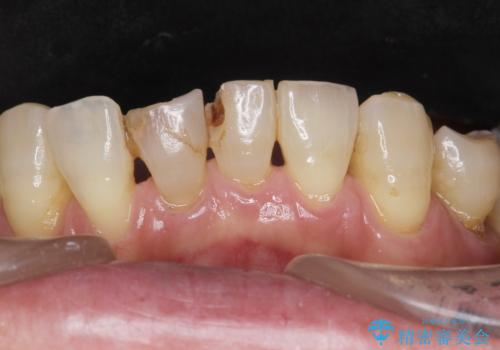

- 右上5番目の歯の被せ物が取れてしまったので治療したいといらっしゃった方の症例です。

虫歯がないことを確認後、セラミックインレーによる修復を行いました。

右上6番目の歯は根尖病変を認めたため、治療を勧めましたが希望されませんでした。

虫歯治療は虫歯の進行度によって処置が変わってきます。

虫歯が小さければ、インレー・クラウン等による修復・補綴処置を行うだけで済みます。

しかし虫歯が大きくなると神経処置や抜歯等をしなければならない場合もあります。

ですので虫歯治療においては早期発見・早期治療が肝要です。